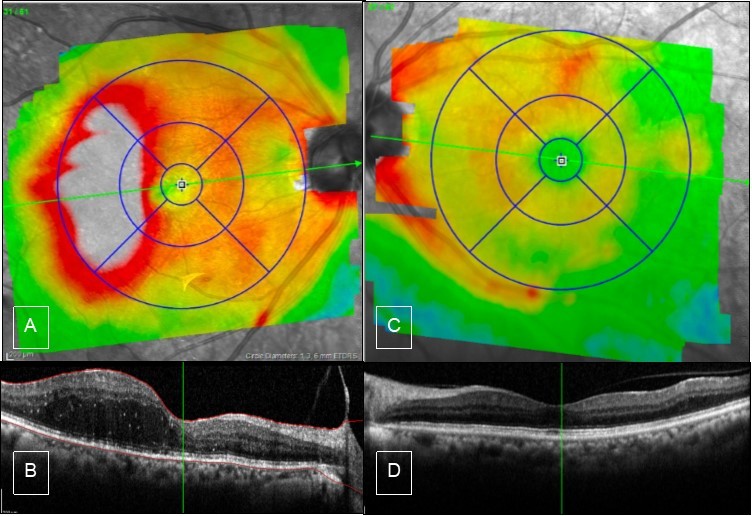

Figure 2.Case 1, OCT, OU. A & B) Right eye showed edema of the temporal macula involving fovea, there is PVD from the macula but still attached to the optic nerve. C & D) Left eye has partial PVD, otherwise it is unremarkable.

Case 1, OCT, OU.  A & B) Right eye showed edema of the temporal macula involving fovea, there is PVD from the macula but still attached to the optic nerve. C & D) Left eye has partial PVD, otherwise it is unremarkable.